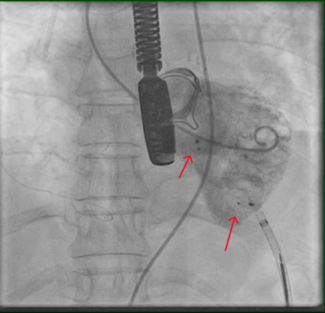

transient ischemic attacks, sick sinus syndrome with pacemaker placement, bilateral renal transplants secondary to glomerulonephritis and bovine aortic valve replacement, initially presented with acute onset of facial swelling. Imaging from an outside facility demonstrated superior vena cava compression from the left subclavian vein, which was thought to be related to occlusive thrombus on his pacemaker wires. He was placed on anticoagulation, instructed to sleep at a  45° angle and brought to the catheterization lab, where balloon angioplasty of the left subclavian and innominate veins was performed, despite not finding a significant stenosis in this area. It was thought that the anticoagulation had resulted in resolution of clot burden prior to the procedure. The patient was seen in follow-up two weeks later with return of his facial swelling while sleeping flat. This usually resolved during the course of the day with normal activities. He was continued on anticoagulation and followed clinically. He presented one month later with sweats, abdominal pain and flu-like symptoms. Further imaging revealed a large right atrial mass with hypermetabolic activity on positron emission tomography scan (Figures 1A, 1B and 2). The patient was referred to cardiac catheterization for a tissue diagnosis.

45° angle and brought to the catheterization lab, where balloon angioplasty of the left subclavian and innominate veins was performed, despite not finding a significant stenosis in this area. It was thought that the anticoagulation had resulted in resolution of clot burden prior to the procedure. The patient was seen in follow-up two weeks later with return of his facial swelling while sleeping flat. This usually resolved during the course of the day with normal activities. He was continued on anticoagulation and followed clinically. He presented one month later with sweats, abdominal pain and flu-like symptoms. Further imaging revealed a large right atrial mass with hypermetabolic activity on positron emission tomography scan (Figures 1A, 1B and 2). The patient was referred to cardiac catheterization for a tissue diagnosis.

Two 8 French (Fr) sheaths (Cordis Corporation, Warren, New Jersey) were  placed in the right femoral vein. A right atrial angiogram was performed with a 6 Fr pigtail catheter (Cordis Corporation) (Figure 3). An 8 Fr Acuson AcuNav intracardiac echo probe (Siemens Medical USA, Malvern, Pennsylvania) was inserted into the right atrium. This was used to visualize the mass (Figure 4). A Mullins sheath (Medtronic, Inc., Minneapolis, Minnesota) was used to guide biopsy forceps (Argon Medical, Athens, Texas) to obtain specimens from the right atrial mass (Figure 5).

placed in the right femoral vein. A right atrial angiogram was performed with a 6 Fr pigtail catheter (Cordis Corporation) (Figure 3). An 8 Fr Acuson AcuNav intracardiac echo probe (Siemens Medical USA, Malvern, Pennsylvania) was inserted into the right atrium. This was used to visualize the mass (Figure 4). A Mullins sheath (Medtronic, Inc., Minneapolis, Minnesota) was used to guide biopsy forceps (Argon Medical, Athens, Texas) to obtain specimens from the right atrial mass (Figure 5).